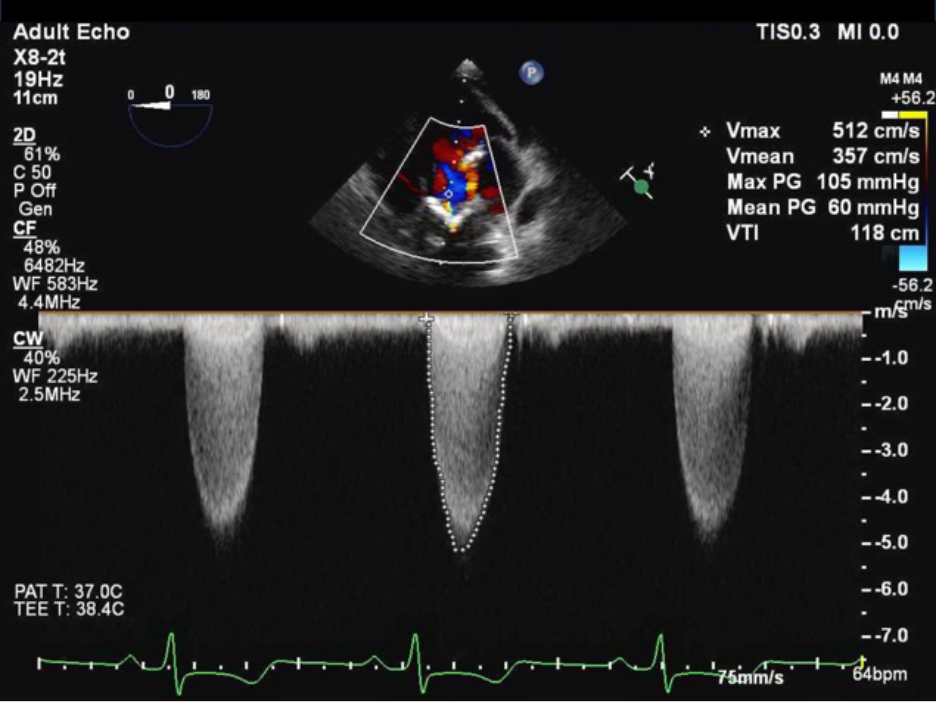

CWD: the echo probe uses two different crystals to continuously send and receive sound waves. By continuously sending and receiving sound waves, all velocities can be measured through the cursor line, but location of the highest velocity cannot be determined. This is known as range ambiguity. CWD is used for stenotic lesions because we assume that the highest velocity will be in the narrowest location in the line of the cursor.

Figure 5

Figure 5. CWD through the aortic valve TEE.